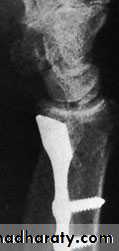

If there is displacement it is reduced, and the wrist is held in ulnar deviation by a plaster slab round the outer forearm extending from below the elbow to the metacarpal necks. Imperfect reduction may lead to osteoarthritis; therefore if closed reduction is imperfect the fragment should be screwed back, or held with K-wires.FRACTURE-SUBLUXATION (BARTON’SFRACTURE)1-volar barton2-dorsal barton

COMMINUTED INTRA-ARTICULARFRACTURES IN YOUNG ADULTS

In the young adult, a comminuted intra-articular fractureis a high energy injury. A poor outcome will result unless intra-articular congruity, fracture alignment and length are restored and movements started as soon as possible. For these patients a much higher standard must be set than would be accepted for the typical osteoporotic fracture. In addition to the usual posteroanterior and lateral x-rays, oblique views and often CT scans are useful to show the fragment alignment. The simplest option is a manipulation and cast. If the anatomy is not restored, then an open reduction may be necessary. The medial complex must be anatomically reduced, which may require open reduction through dorsal and palmar approaches and a combination of wires, plates, screws and bone grafts.